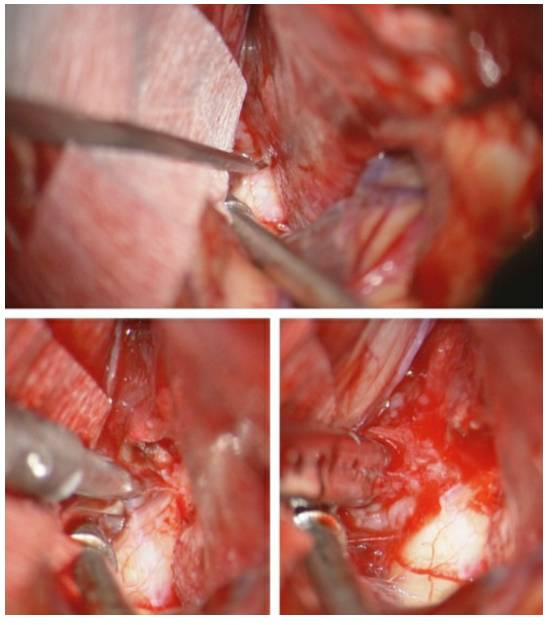

图11. 所有MCA血管均锐性方式从肿瘤包膜外游离出来,并用棉片加以保护(上图)。应尽可能避免钝性分离。最重要的是,在处理血管前应清楚地识别肿瘤的供血动脉和过路血管。可用罂粟碱浸泡的明胶海绵处理过路血管,以减轻血管痉挛。高倍放大的术中视野示范如何将M2分支血管从肿瘤(T)表面分离(下图)。

尽管在影像上,肿瘤包绕血管的现象很常见,但是肿瘤与MCA分支之间完整的蛛网膜平面有助于将血管从肿瘤表面游离出去。但是如果肿瘤与血管粘连过于紧密,应遗留一薄层肿瘤组织,以起到保护作用,避免发生血管痉挛。

图12. 仔细地将肿瘤前极游离出来,对于识别位于颅底的视神经和ICA是非常重要的(上图)。沿着蝶骨翼内侧走形,可以大致定位视神经管和ICA。在下方的图片中,术中将肿瘤的前额部切除后,吸引器尖端所对的就是视神经和颈内动脉的位置。电凝后残留的肿瘤组织位于天幕边缘。

图13. 小心松动内侧的包膜,锐性分离可以游离出视神经和近端ICA。切开镰状韧带以松解视神经。可见后交通动脉起源自ICA后壁。该血管可用于指示动眼神经。如果肿瘤与神经或血管粘连紧密,需避免过度的操作和钝性分离,留下一薄层肿瘤组织。即便轻柔地处理动眼神经和天幕周围的肿瘤组织,大多数患者术后仍会出现一过性动眼神经和滑车神经麻痹。应尽量避免在这些血管周围电凝天幕。